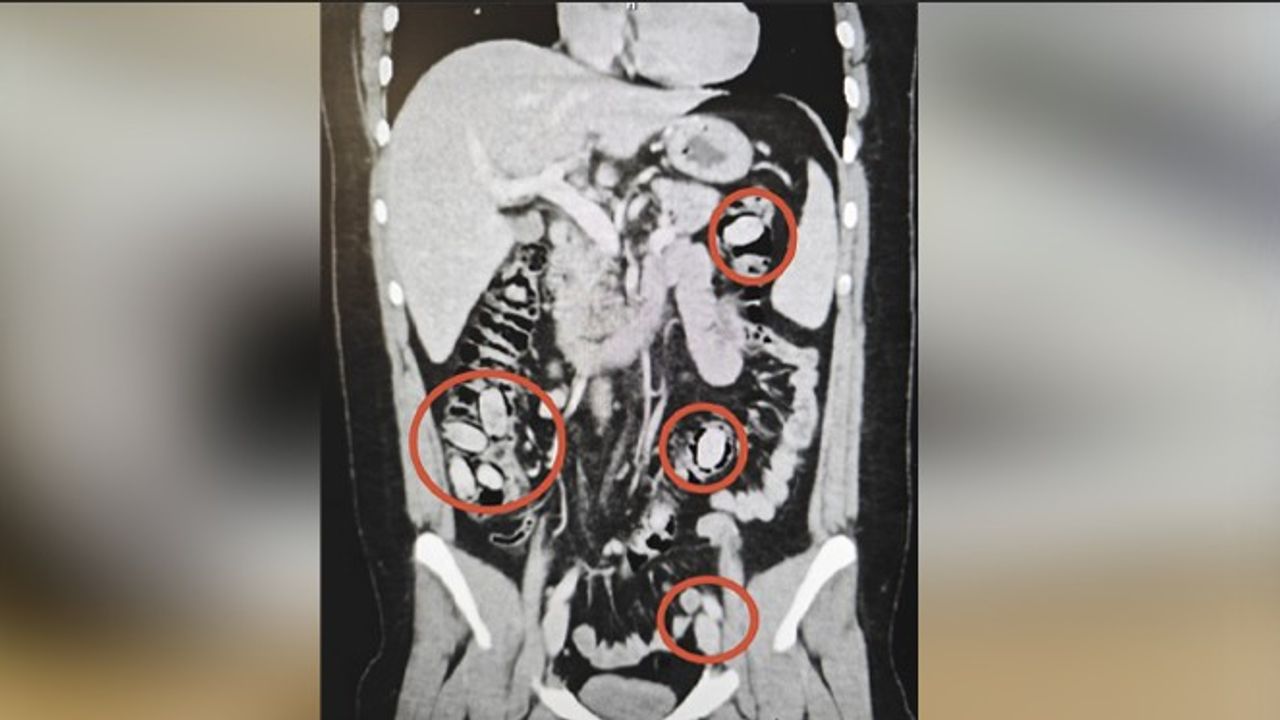

Hastanede yapılan detaylı tetkikler sonucunda şahsın yutmak suretiyle midesinde metamfetamin kapsülleri taşıdığı belirlendi. Cerrahi müdahale ile kapsüller güvenli bir şekilde çıkarıldı. Tedavisi tamamlanan şahıs, çıkarıldığı mahkemece tutuklanarak cezaevine gönderildi. Emniyet yetkilileri, operasyon sayesinde uyuşturucu maddelerin Eskişehir’de piyasaya sürülmeden ele geçirildiğini ve halkın güvenliğinin sağlandığını vurguladı.